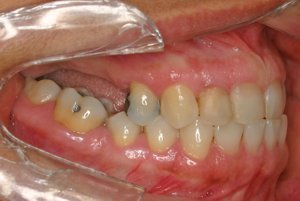

Enxerto de seio maxilar